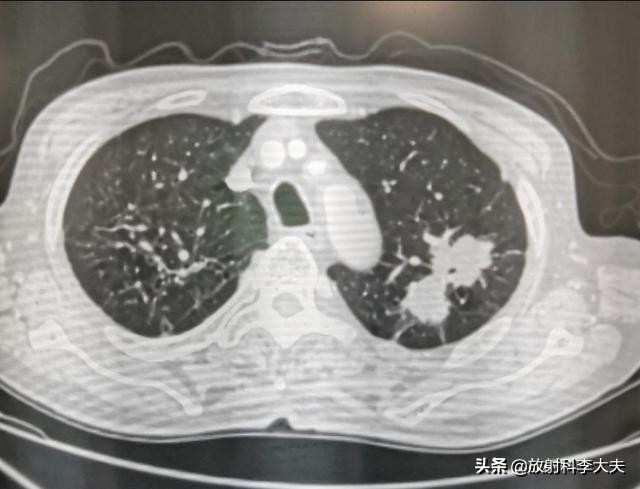

双肺多发的病灶,有的已经钙化,陈旧的结核灶。但是,左肺上叶一个哑铃形状的病变,引起重视。

左肺上叶病变可见分叶,尖后段支气管欠通畅。影像上考虑有肺癌的可能,但是鉴于有肺结核病史,还需要慎重考虑。